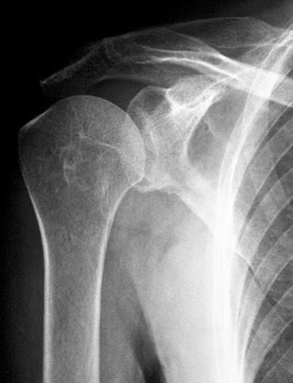

Запитання 9

ПІСЛЯ АВТОМОБІЛЬНОЇ АВАРІЇ НА РЕНТГЕНОГРАМІ ВИЯВЛЕНО ПЕРЕЛОМ КІСТКИ В ДІЛЯНЦІ ХІРУРГІЧНОЇ ШИЙКИ. ЯКА КІСТКА МАЄ ТАКУ ШИЙКУ?

варіанти відповідей

Запитання 18

РОЗПІЗНАЙТЕ НА РЕНТГЕНОГРАМІ СУГЛОБ, ЩО МАЄ МІЛКУ СУГЛОБОВУ ЗАПАДИНУ І СКРІПЛЕНИЙ ПЕРЕВАЖНО М'ЯЗАМИ, ТОМУ ТУТ ВІДНОСНО ЧАСТО БУВАЮТЬ ВИВИХИ.

РОЗПІЗНАЙТЕ НАЙРУХОМІШИЙ СУГЛОБ ТІЛА ЛЮДИНИ, А ТАКОЖ СУГЛОБИ І КІСТКИ З ПЕВНИМИ ДІАГНОЗАМИ.

Запитання 28

ПЕРЕЛОМ ЯКОЇ КІСТКИ І В ЯКІЙ ЇЇ ЧАСТИНІ ВИ БАЧИТЕ?

ГОЛОВКИ HUMERUS

ДИСТАЛЬНОГО ЕПІФІЗА HUMERUS

ШИЙКИ FEMUR

ГОЛОВКИ FEMUR

ГОЛОВКИ RADIUS

ПРОКСИМАЛЬНОГО ЕПІФІЗА HUMERUS

ХІРУРГІЧНОЇ ШИЙКИ HUMERUS

АНАТОМІЧНОЇ ШИЙКИ HUMERUS

Запитання 38

ДЕ ВИ БАЧИТЕ СУГЛОБ, ЯКИЙ ЗАБЕЗПЕЧУЄ РУХИ ПЛЕЧА.

Запитання 46

ДЕ ВИ БАЧИТЕ СУГЛОБ, ЩО ЗАБЕЗПЕЧУЄ РУХИ ПЛЕЧА?

Запитання 48

ШИЙКА КІСТКИ ГЛИБОКО МІСТИТЬСЯ В СУГЛОБОВІЙ ПОРОЖНИНІ, КАПСУЛА МІЦНА, СКРІПЛЕНА БІЧНИМИ ЗВ'ЯЗКАМИ, ЩО СПРИЯЄ ПЕРЕЛОМАМ. РОЗПІЗНАЙТЕ СУГЛОБ.